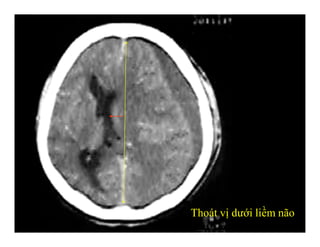

-Thoát vị dưới liềm (Subfalcial H.)

-Thoát vị dưới liềm: hồi đai

qua dưới bờ tự do liềm não

Đường giữa lệch.

-Ép não thất cùng bên

-Có thể rộng não thất đối bên

-Nhồi máu động mạch não

trước

THOÁT VỊ DƯỚI LIỀM NÃO

-Thoát vị dướiliềm: hồi đai qua dưới bờ tự do liềm não Đường giữa lệch. -Ép não thất cùng bên -Có thể rộng não thất đối bên -Nhồi máu động mạch não trước THOÁT VỊ DƯỚI LIỀM NÃO